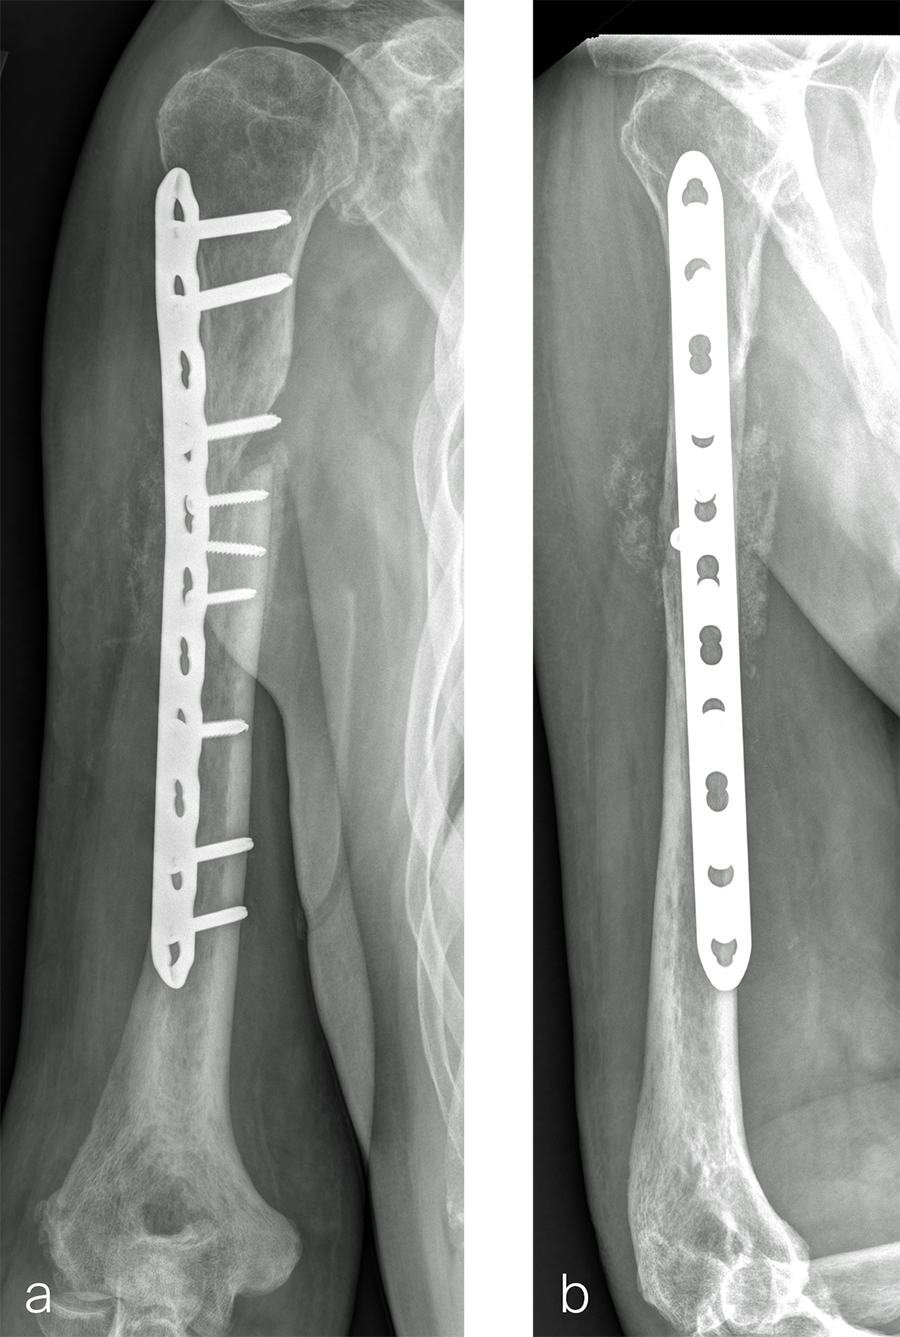

After debridement and resection of the pseudarthrosis, we accessed the distal segment of the humeral canal and used a small caliber RIA 2 reamer head to harvest intramedullary bone graft (Fig 8) for final plate fixation (Fig 9).